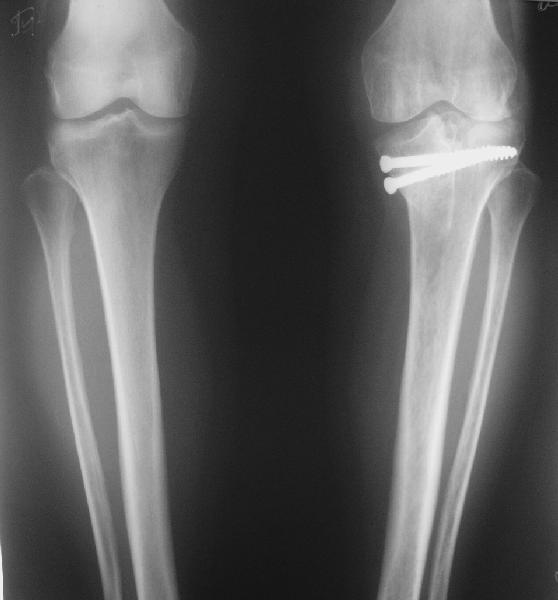

При планировании операции возникли разногласия, на каком уровне делать остеотомию. То ли поднимать внутренний мыщелок, т.е. делать остеотомию через сустав, то ли обойтись внесуставной коррекцией оси.

Второй вариант менее травматичен, но конгруэнтность сустава при этом останется нарушенной, улучшится только ось конечности.

Допустима ли такая коррекция, или все-таки правильнее не менять взаимоотношения наружного мыщелка с диафизом, а поднять именно внутренний мыщелок?